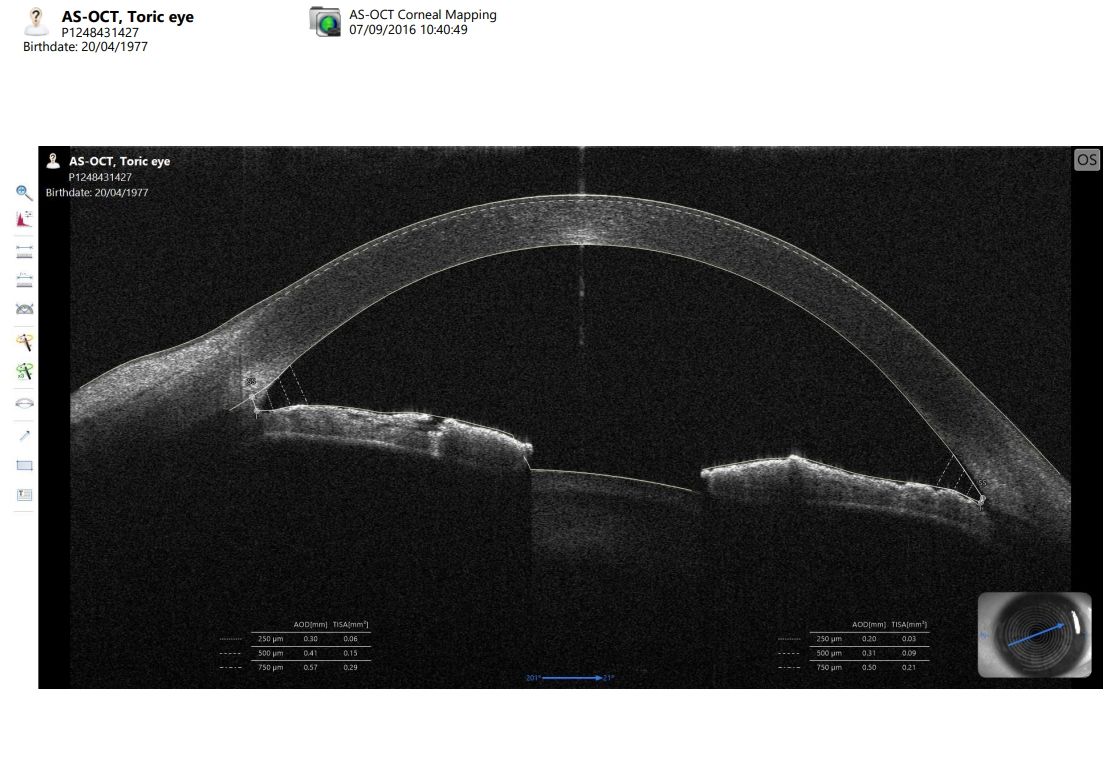

CSO MS-39 Anterior Segment OCT

he MS-39 delivers high clarity cross-sectional images, with a 16 mm diameter, along with the many details of the cornea structure and information about the epithelium layer, pachymetry, elevation, curvature, and dioptric power of both corneal surfaces.

- Anterior Chamber Measurements

- High resolution corneal imaging

- Gonioscopy and Glaucoma analysis